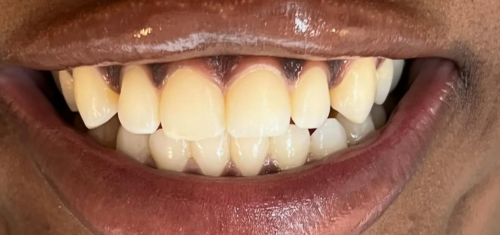

Before And After Dental Treatment

Before / After

From stained or misaligned teeth to a radiant, confident smile, our results speak for themselves. See the difference professional dental treatment can make — and imagine what we can do for you.